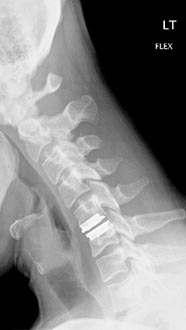

35 year old man presenting with severe neck pain with radiation down the right arm with right bicep weakness. MRI with large right C5-6 disc extrusion.

Postoperative xrays after C5-6 anterior cervical disc replacement. Complete resolution of arm pain and full painless range of motion of his neck.